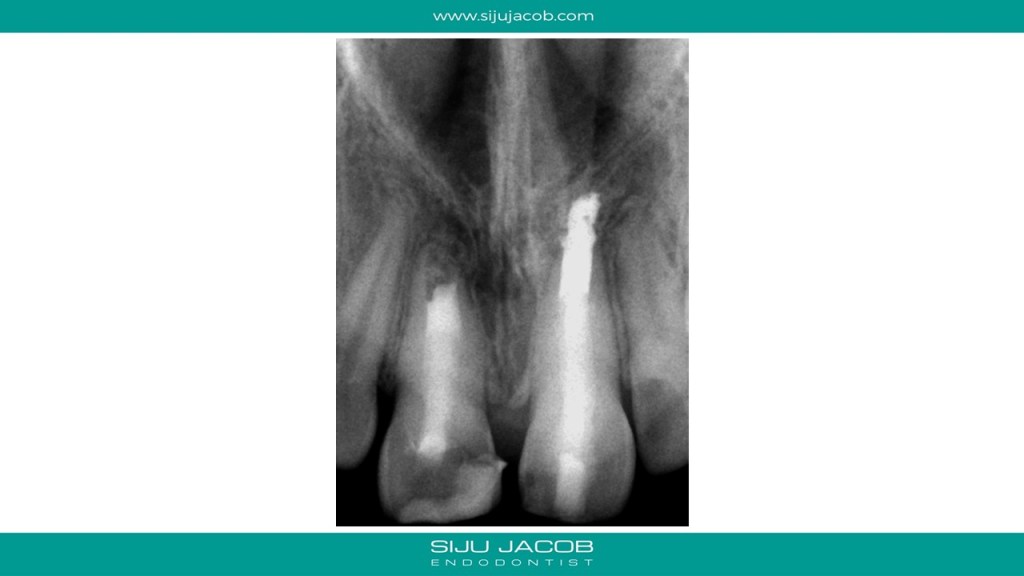

This was probably the largest lesion I ever treated. It had several interesting characteristics. It would be tough to explain with just pics. So, I made it into a short presentation